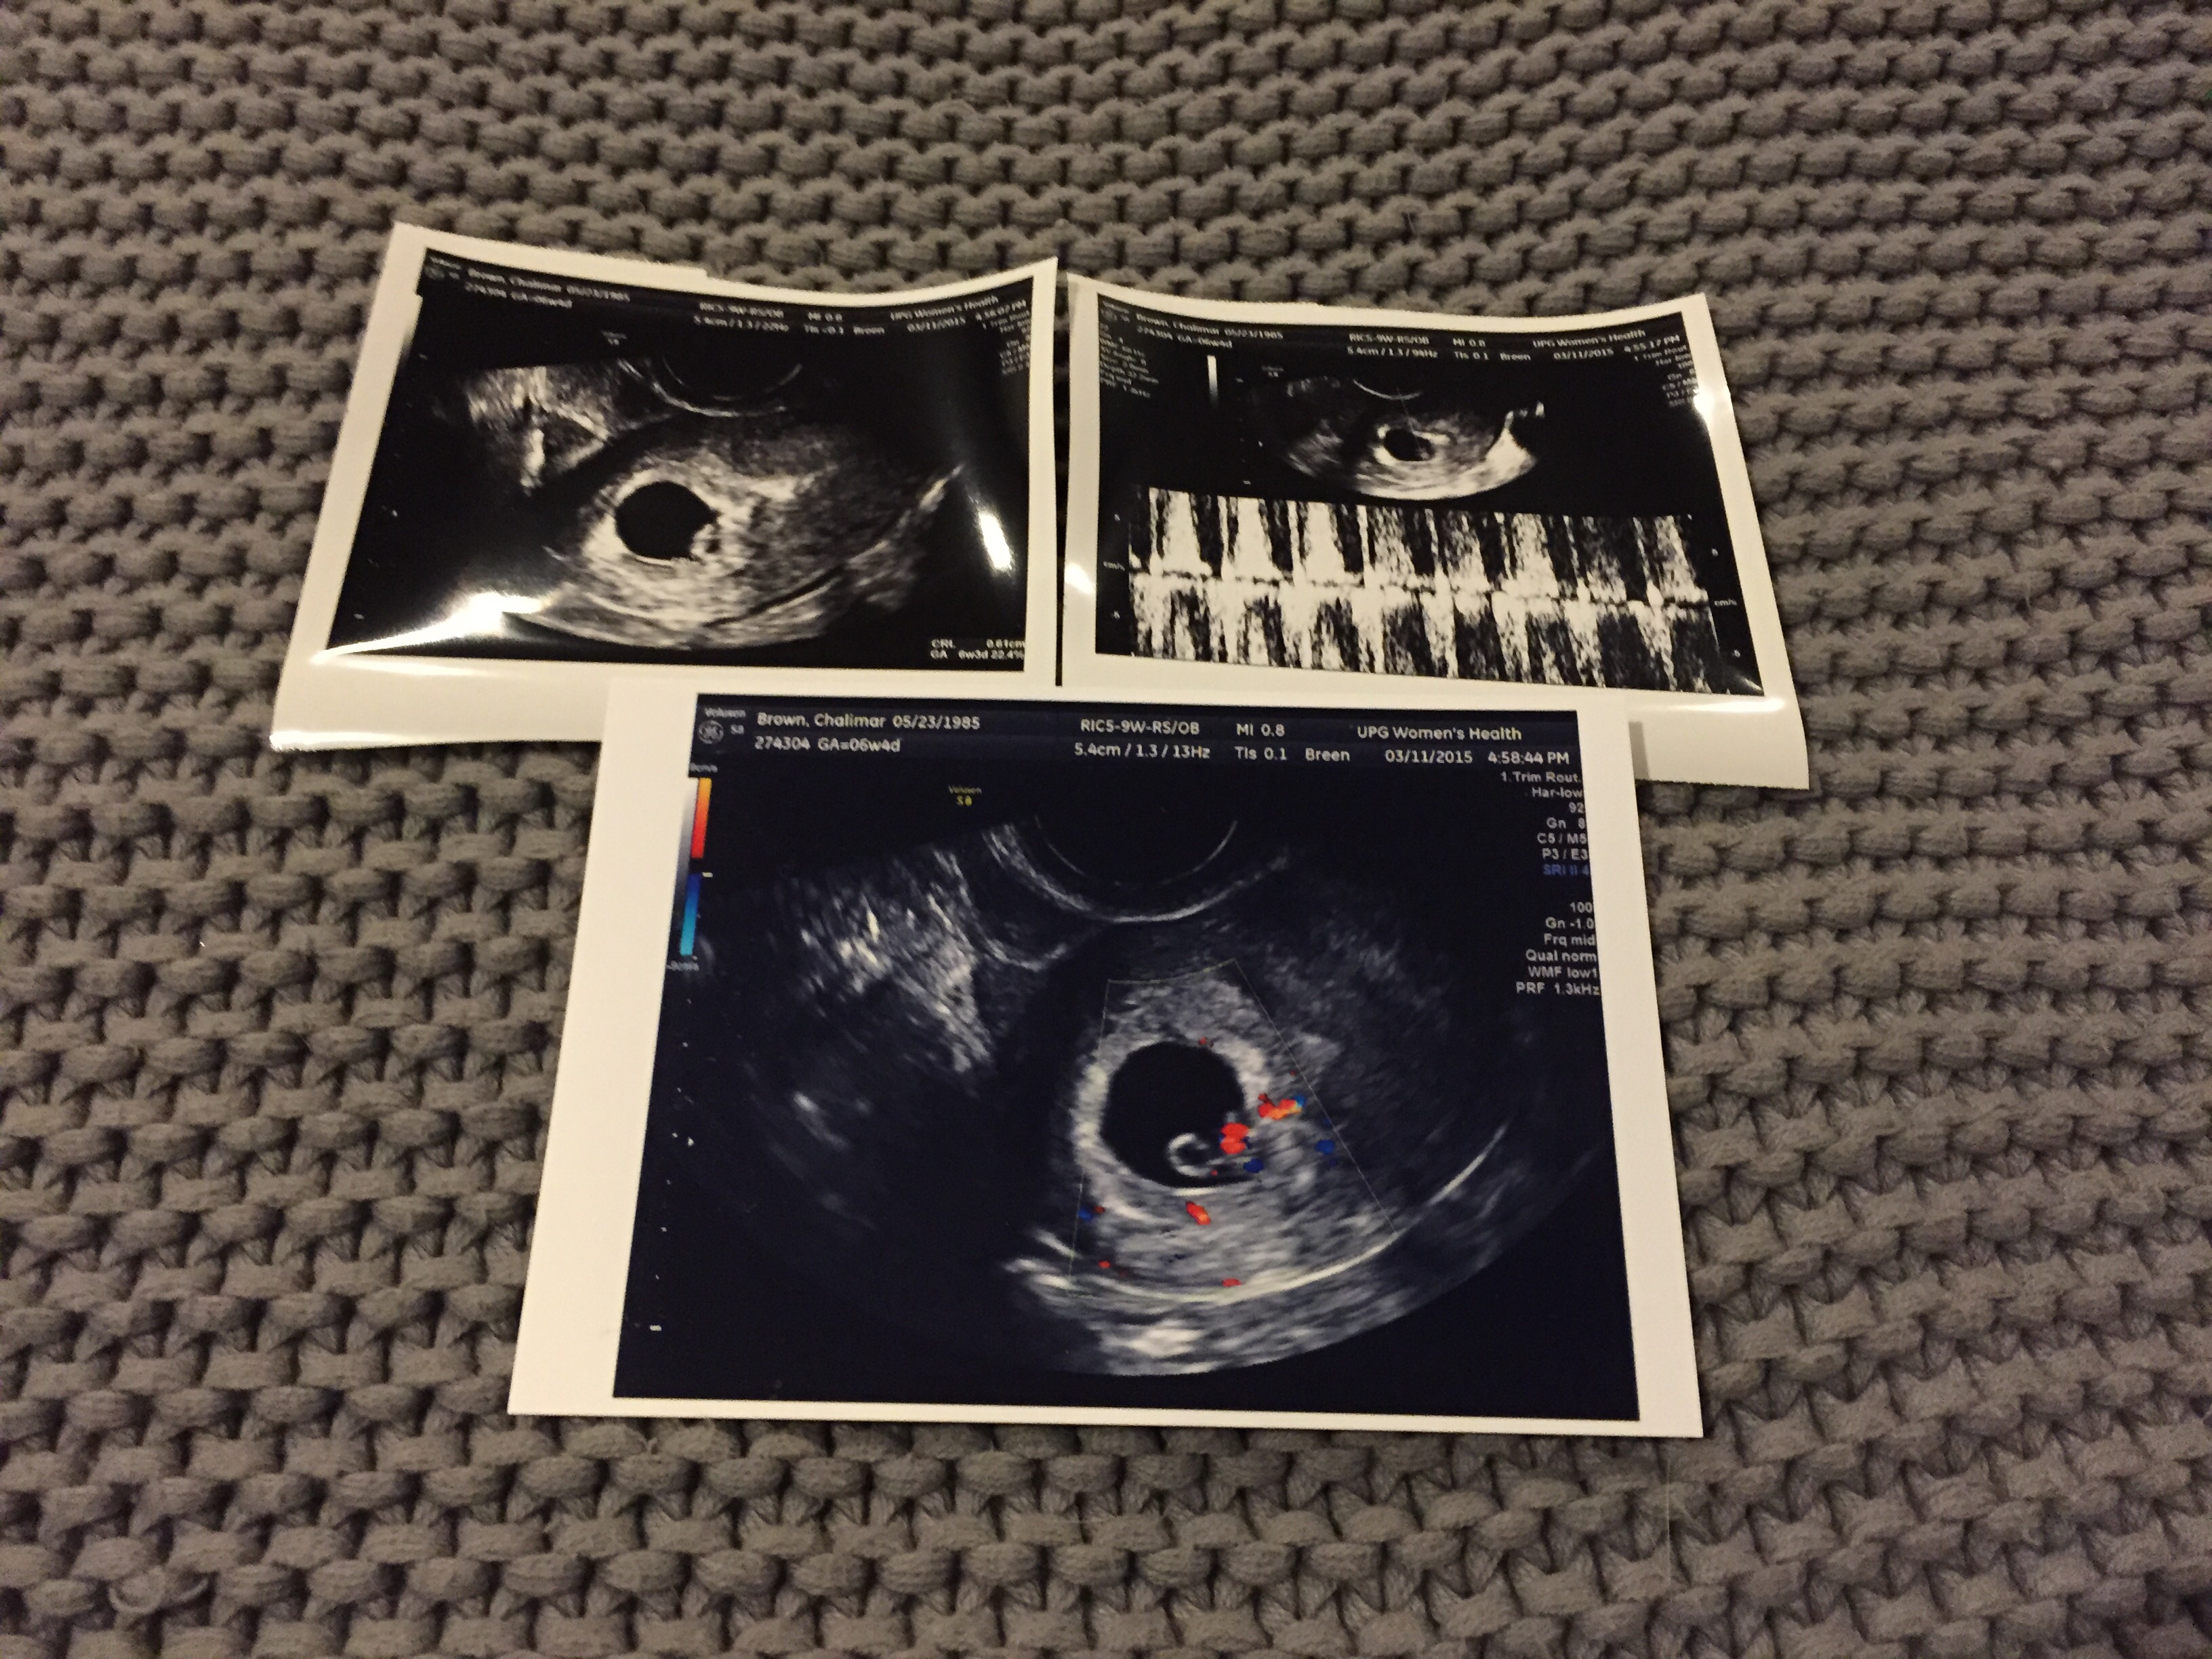

Baby Walton today (3/11) at 9w4d gestational age is +1 day! He even stretched his arm out during the U/S and we saw the heartbeat!! HR is 162 bpm so in love with this tiny thing!!